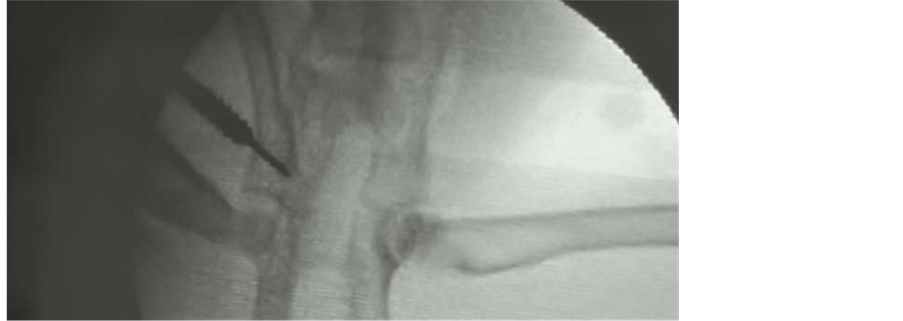

Our hypothesis is that residual dysplasia may be improved by provoking selective growth arrest of the ilioischial arm of the triradiate cartilage (posterior epiphysiodesis). The aim of this study was to assess the possibility to obtain morphological changes in the acetabulum through posterior epiphysiodesis to the triradiate cartilage by the percutaneous placement of a 2.7-mm cannulated screw under imaging intensifier guidance in a pilot-model, experimental study in rabbits (Figure 1(a), Figure 1(b)).

A pilot study was conducted in 3-week-old New Zealand (number of animals: 20, 10 males and 10 females) rabbits submitted to unilateral surgery in one hip while the contralateral hip of the same group was used as a control. The operative side was chosen by random allocation. Posterior selective epiphysiodesis of the ilioischial arm of the extra articular portion of the triradiate cartilage was performed guided by an imaging intensifier using a 2.7-mm cannulated screw at three weeks of life (Figure 1(a), Figure 1(b)).

Figure 1. (a) A posterior oblique view of the coxis. The triradiate cartilage is marked and the red arrow identifies the area where the 2.7-mm cannulated screw was placed for the selective epiphysiodesis to the extraarticular portion of the ilioischialarm. (b) Percutaneous placement of a 2.7-mm cannulated screw under imaging intensifier.